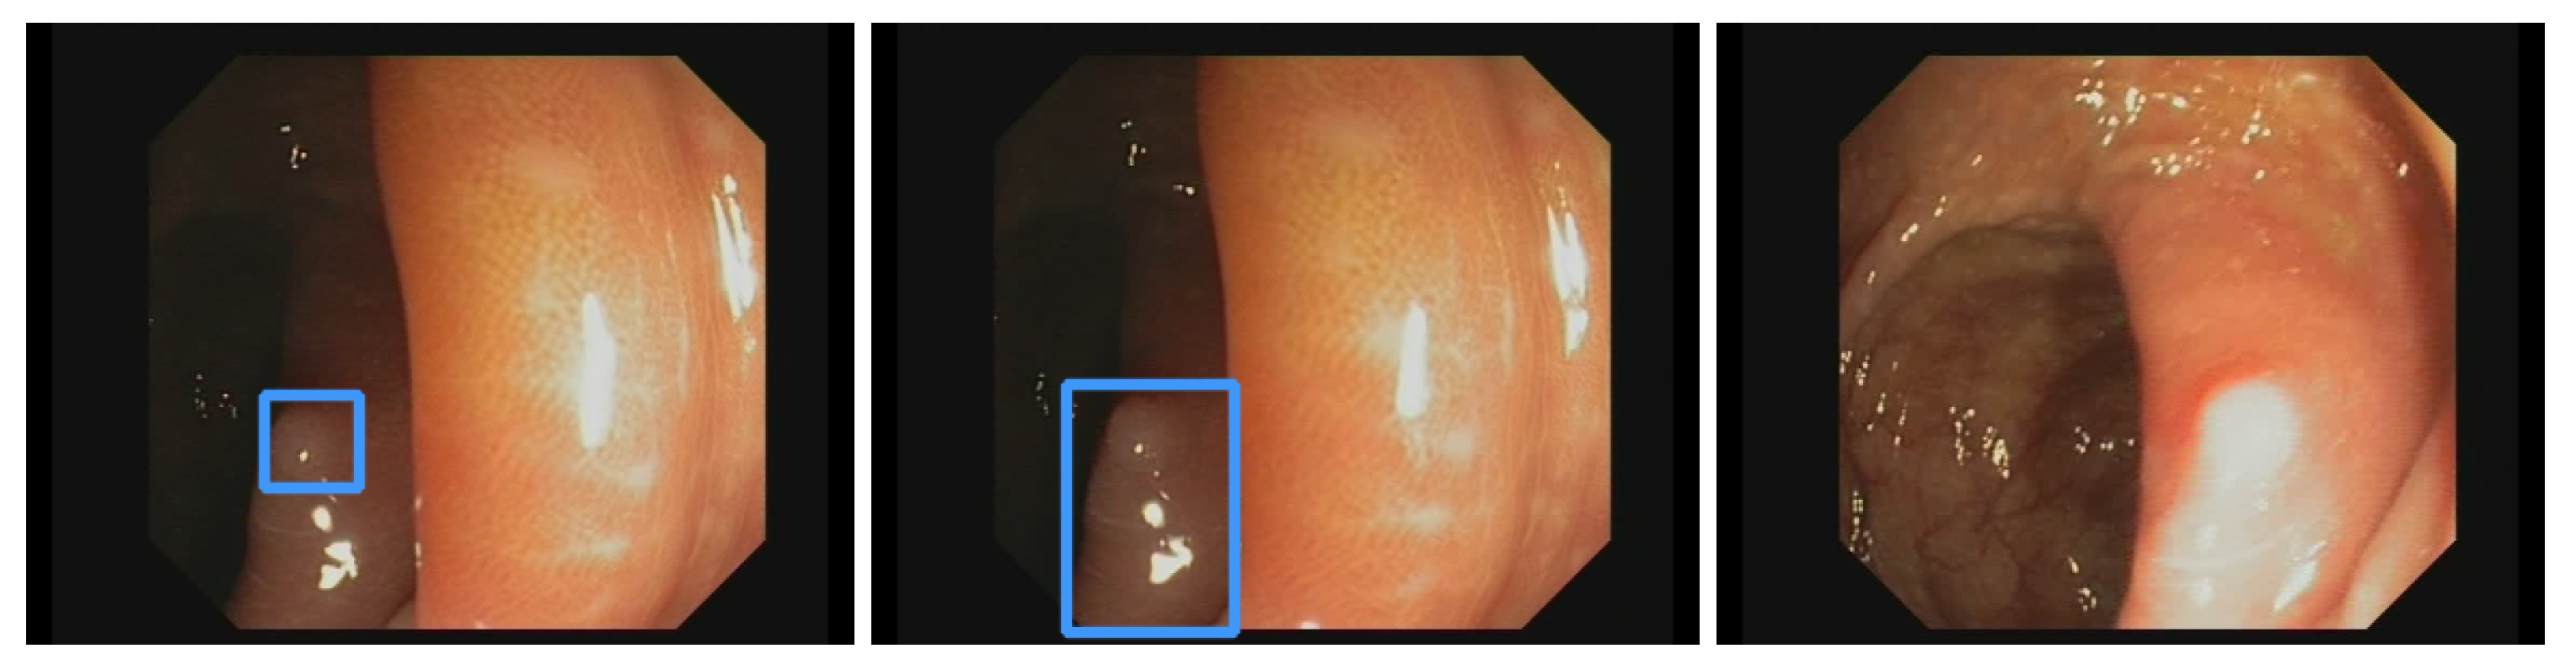

Additionally, the polyp-detection system was publicly funded and developed by computer engineers and endoscopists in the same workgroup to ensure high-quality polyp detection. Figure 1 shows the results of the polyp-detection system. To overview existing work and properly allocate our paper in the literature, we describe a brief history from general polyp detection with handcrafted features to state-of-the-art polyp detection with deep learning techniques.

Obtaining qualitative data on an appropriate scale is often one of the biggest problems for applying deep learning methods. This is no different for colonoscopy videos/images for polyp detection. The difficulties in the acquisition are due to data protection issues on the one hand and the expensive and time-consuming but necessary annotation of the data by experienced medical experts. Therefore, for developing our model, we use our own data and all the publicly available data we could find on the internet and in the literature. For training our model, we combined the available online sources and our own data to forge a dataset of 506,338 images. Figure 2 shows an overview of the data material. The details about creating our own dataset will follow below. All data consist of images and bounding box coordinates of boxes referring to the image. For a listing of publicly available datasets we used for training, we show the following overview:

We built a team of advanced gastroenterologists and medical assistants. We created a dataset of 506,338 images, including the open-source images listed above. Figure 2 shows an overview of the different datasets. Our dataset consists of 361 polyp sequences and 312 non-polyp sequences. The polyp sequence was selected in high quality as we were generally only annotating the first 1–3 s of the polyp’s appearance, which is critical for detecting polyps in a real clinical scenario. We combined training material from six centers involving three different endoscope manufacturers, named Karl Storz GmbH und Co. KG (Storz), Ricoh Company Ltd. (Pentax), and Olympus K.K. (Olympus). Overall, 91% of the images are from Olympus, 5% are from Pentax, and 4% are from Storz processors. We create a dataset of 24 polyp sequences involving 12,161 images and 24 non-polyp sequences involving 10,695 images for the test data (EndoData). Therefore, the test data consist of an additional 22,856 images. We assured the independency of the test data as EndoData is created from a different clinic with different polyps and patients compared to the training data.